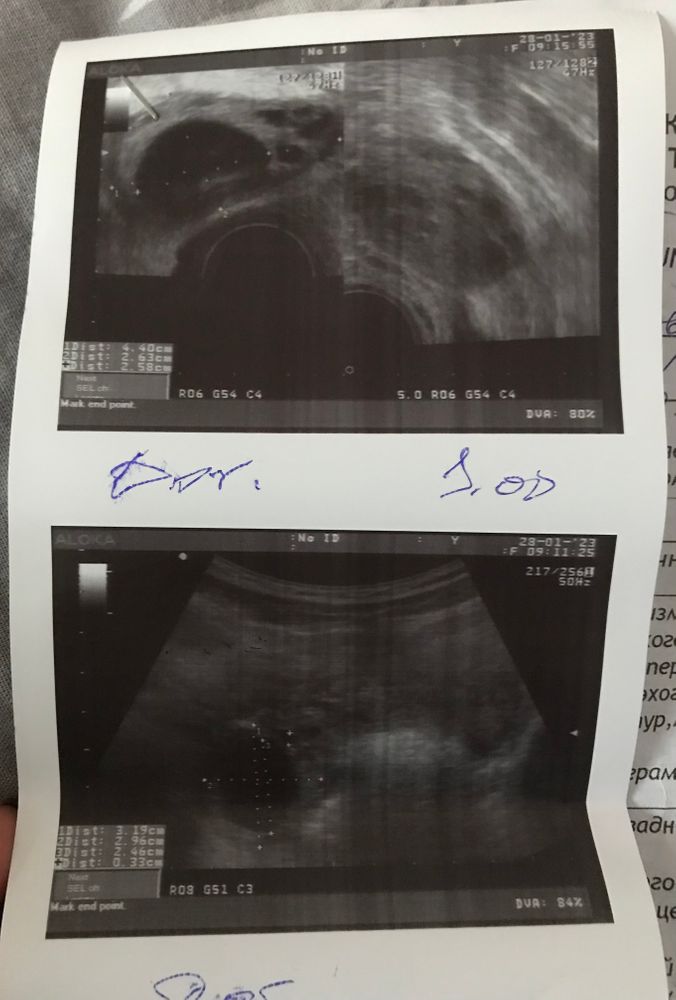

Здравствуйте девушки. После узи не могу понять какой из снимков это «трансабминальное узи»(брюшная полость)

а какое «трансвагинальное» (вагинально). Или это одно какое-то просто с разных ракурсов.

Где картинка четче - это вагинальное. Предположительно, верхнее